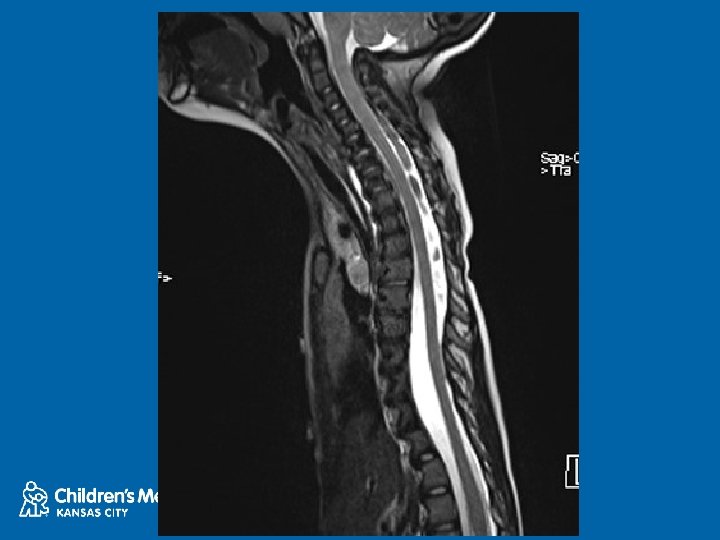

NF 1 and Dural Ectasia • Frequently thoracic • Can be relatively protective, increased SAC • Posterior scalloping commonly associated with dural ectasia • Lateral and anterior scalloping commonly result of primary mesodermal dysplasia • Tsirikos AI 2004 • Anterior dural ectasia and dislocation of the spine • Winter 1991 28